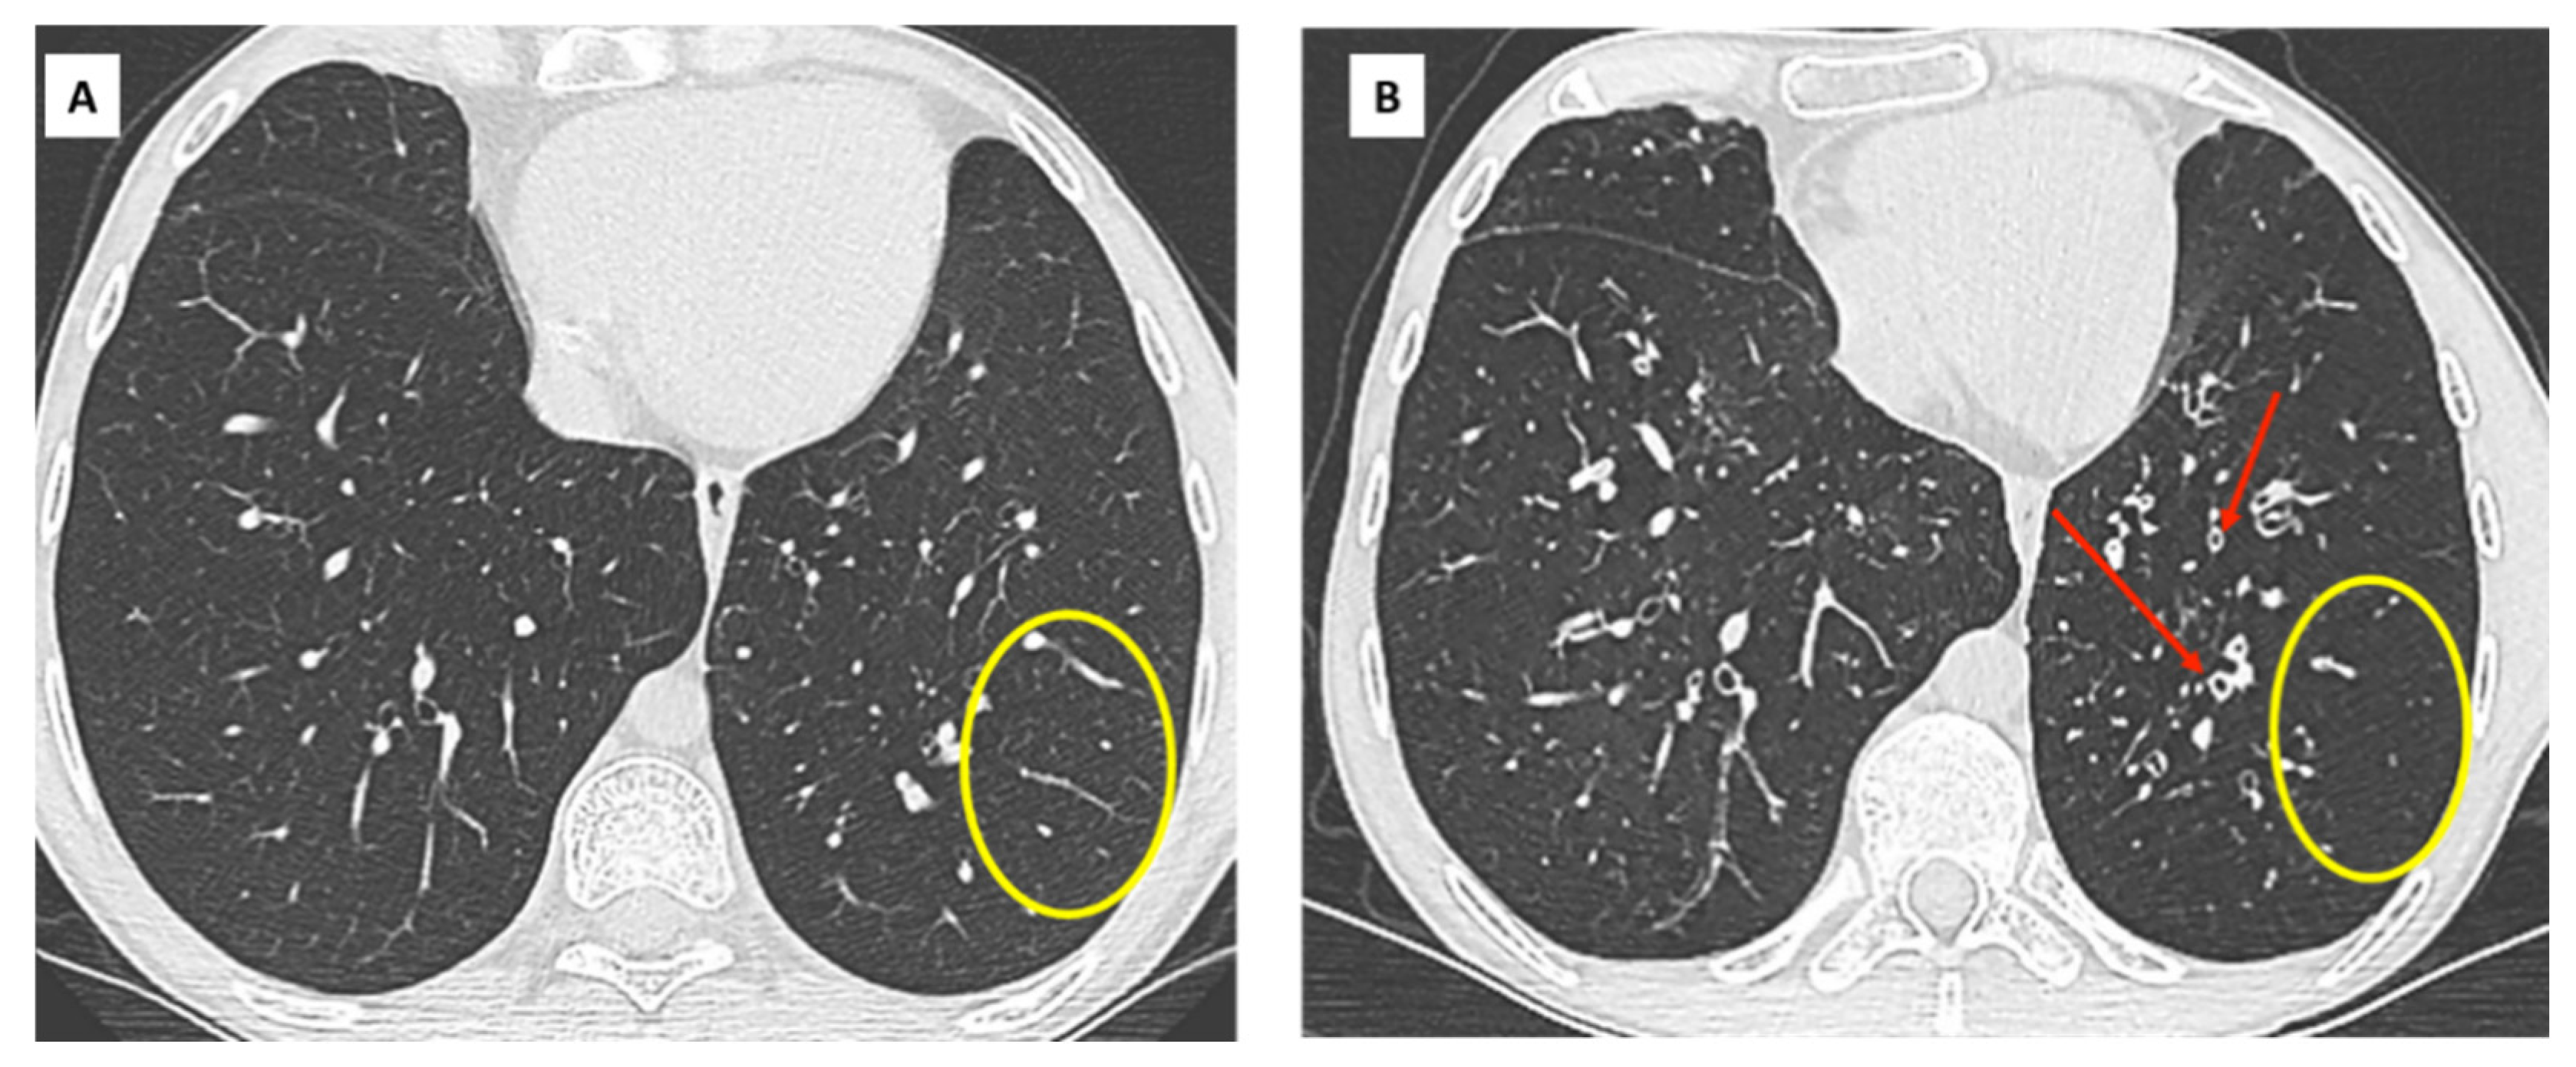

- Hota, P.; Dass, C.; Kumaran, M.; Simpson, S. High-resolution CT findings of obstructive phenotypes of chronic lung allograft dysfunction: More than just bronchiolitis oblierans syndrome. AJR Am. J. Roentgenol. 2018, 211, W13–W21. [Google Scholar] [CrossRef] [PubMed]

- Bankier, A.A.; Van Muylem, A.; Knoop, C.; Estenne, M.; Gevenois, P.A. Bronchiolitis Obliterans Syndrome in Heart-Lung Transplant Recipients: Diagnosis with Expiratory CT. Radiology 2001, 218, 533–539. [Google Scholar] [CrossRef]

- Siegel, M.J.; Bhalla, S.; Guttierrez, F.R.; Hildebolt, C.; Sweet, S. Post-lung transplantation bronchiolitis obliterans syndrome: Usefulness of expiratory thin-section CT for diagnosis. Radiology 2001, 220, 455–462. [Google Scholar] [CrossRef] [PubMed]

- de Jong, P.A.; Dodd, J.D.; Coxson, H.O.; Storness-Bliss, C.; Paré, P.D.; Mayo, J.R.; Levy, R.D. Bronchiolitis obliterans following lung transplantation: Early detection using computed tomographic scanning. Thorax 2006, 61, 799–804. [Google Scholar] [CrossRef]

- Konen, E.; Gutierrez, C.; Chaparro, C.; Murray, C.P.; Chung, T.; Crossin, J.; Hutcheon, M.A.; Paul, N.S.; Weisbrod, G.L. Bronchiolitis obliterans syndrome in lung trnsplant recipients: Can thin-section CT findings predict disease before its clinical appearance? Radiology 2004, 231, 467–473. [Google Scholar] [CrossRef] [PubMed]